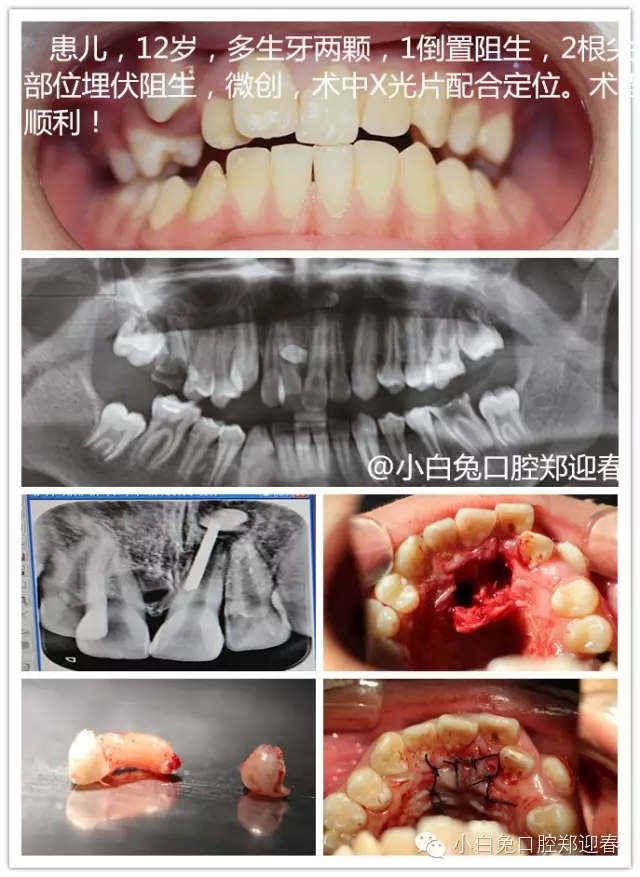

“多生牙”案例集錦(鄭穎春)......

額外牙可發(fā)生于乳牙列,也可發(fā)生于恒牙列,但恒牙列發(fā)生率多于乳牙列。額外牙經(jīng)常在上頜出現(xiàn),上、下頜出現(xiàn)比例為10∶1,可單個(gè)或多個(gè)、單側(cè)或雙側(cè)出現(xiàn),形態(tài)可同正常牙,也可是畸形牙、過(guò)小牙。